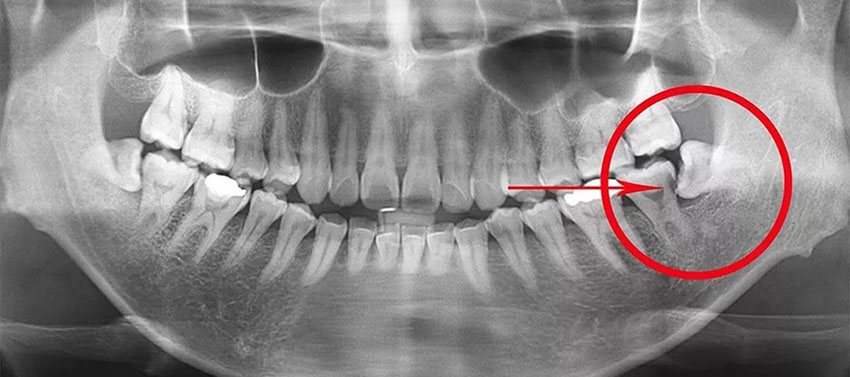

- в каком состоянии находятся ткани кости в тех местах, где в дальнейшем предполагается устанавливать имплантаты.